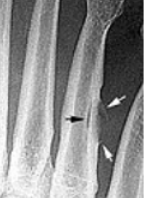

| What do the arrows show? | Stress fracture |

| Describe what has happened at the shaft of the 3rd met | Exuberant periosteal new bone production. May have resulted if a stress fracture was not treated and the patient continued weight bearing activities. |